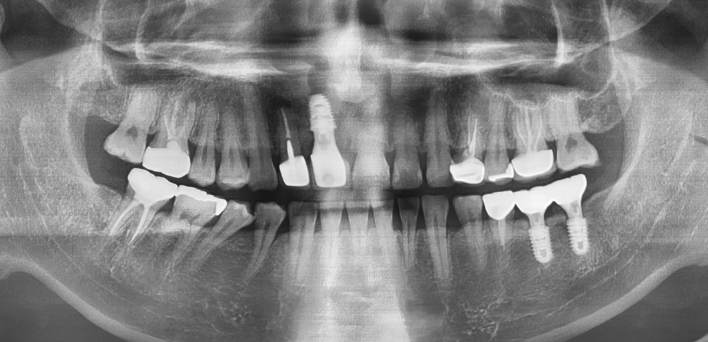

임플란트 : 손 ** 님 (50대)

After After

2020.02.30

위, 아래 6개씩 식립

디지털 풀아치 임플란트

임시 치아라고 조심하라고 하셨는데 수술하고 맛동산까지 먹었습니다.